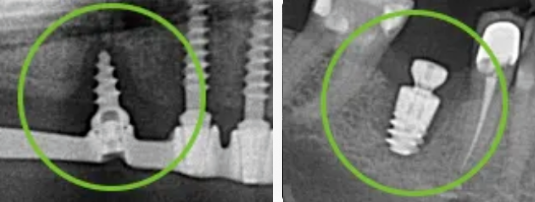

Что такое периимплантит? Периимплантит – воспаление мягких и костных тканей вокруг дентального импланта, приводящее к резорбции (убыли) костной ткани и потере импланта. Периимплантит является одной из самых распространенных причин отторжения имплантов. Как правило, сначала развивается мукозит – воспаление мягких тканей вокруг импланта. При отсутствии своевременного лечения воспалительный процесс распространяется вглубь и поражает костную ткань. Почему развивается периимплантит? 1. Самой частой причиной периимплантита выступает недостаточная ежедневная гигиена полости рта, отсутствие регулярной профессиональной гигиены каждые 6 месяцев. В результате в месте контакта импланта с десной образуется скопление бактериального налета и зубного камня, что провоцирует воспаление тканей вокруг импланта. 2. Также причиной периимплантита, особенно в первые месяцы после имплантации, является несоблюдение пациентом рекомендаций и назначений врача. 3. Врачебные ошибки являются довольно редкой причиной